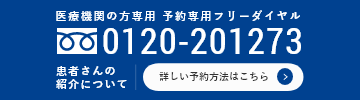

慢性閉塞性肺疾患(chronic obstructive pulmonary disease:COPD)は、以前は肺気腫や慢性気管支炎と呼ばれていた疾患のことで、タバコ煙を主とする有害物質を長期間吸入することによって、末梢気管支や肺胞に慢性炎症が生じ、その結果として空気の通り道が狭くなり、肺胞の破壊も生じて、肺のガス交換が障害される病気です。一度発症すると緩徐に進行し、慢性的な咳や痰、息切れなどで徐々に日常生活に支障を来すようになります(図1)。

図1. COPDの肺病変(胸部CT像)

COPD(右図)では健常人(左図)と比べ黒く大きく抜けている部分(ブラ、のう胞)が全体的に増加しており、肺胞構造が壊れていることが分かります。